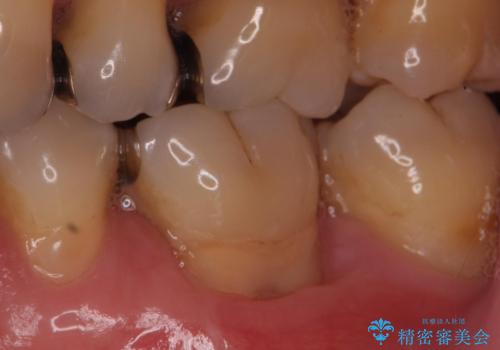

Dr. 岡田康成の症例写真

担当医 岡田康成<2025年10月31日更新>